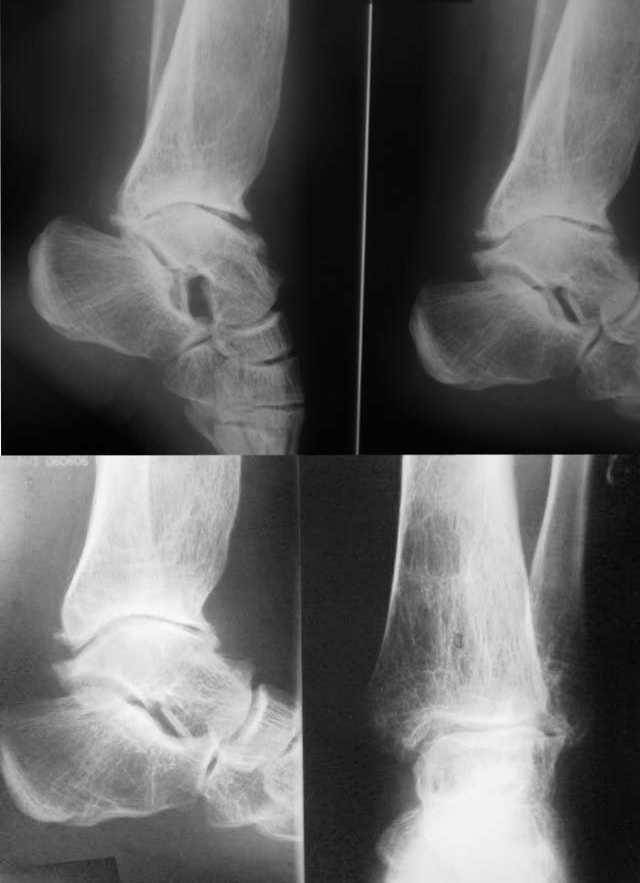

Посттравматическая наружная нестабильность голеностопного сустава у пациентки 30 лет.

Боли не беспокоят. От артродеза отказывается. Боится ограничения движений и хромоты.

Как предотвратить наружный подвывих стопы? Может быть  кто-то может предложить свою помощь?